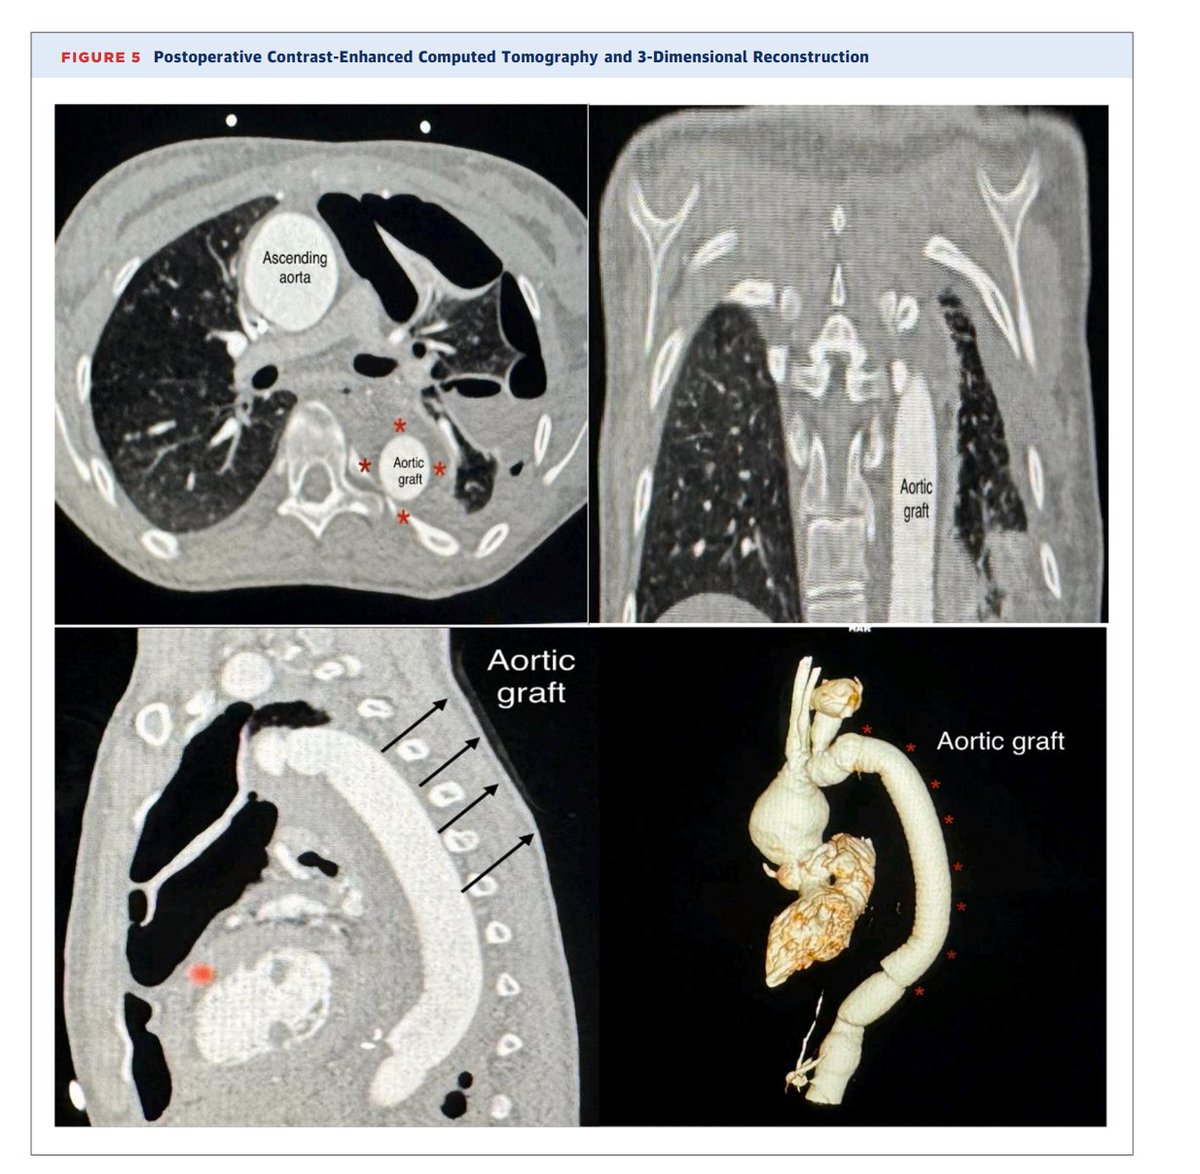

dilated ascending aorta with a clear flap, arch of aorta, and descending aorta down to renal arteries. The plan changed to CT aortography, and the patient was taken to the cardiac OR. The whole aorta was repaired successfully

Arterial aneurysms are among the rare vascular manifestations of HIES. We present a case of a 17-year-old girl who had a known history of HIES since childhood. She had a large thoracic descending aortic aneurysm, which required surgical repair to prevent complications

Hyperimmunoglobulin E syndromes (HIES) are a heterogeneous group of primary immunodeficiencies sharing manifestations including recurrent lung infection and significantly raised serum levels of immunoglobulin E.

New publication, JACC case reports A Huge Thoracic Aortic Aneurysm as a Rare Complication of Hyperimmunog... https://t.co/iiAyH7bCaE